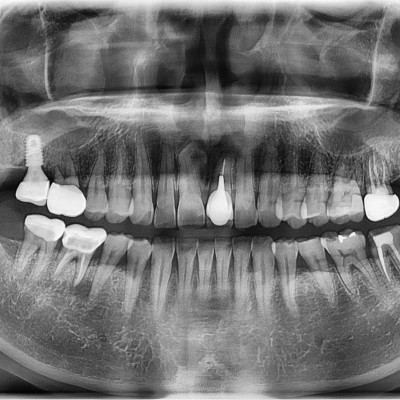

#18,28,48 사랑니 발치 #18,28,48 사랑니 발치 구강 외과 전문의가 당일 발치했습니다. ---------------------..

작성자 이턱이 작성일 02-11 조회 48